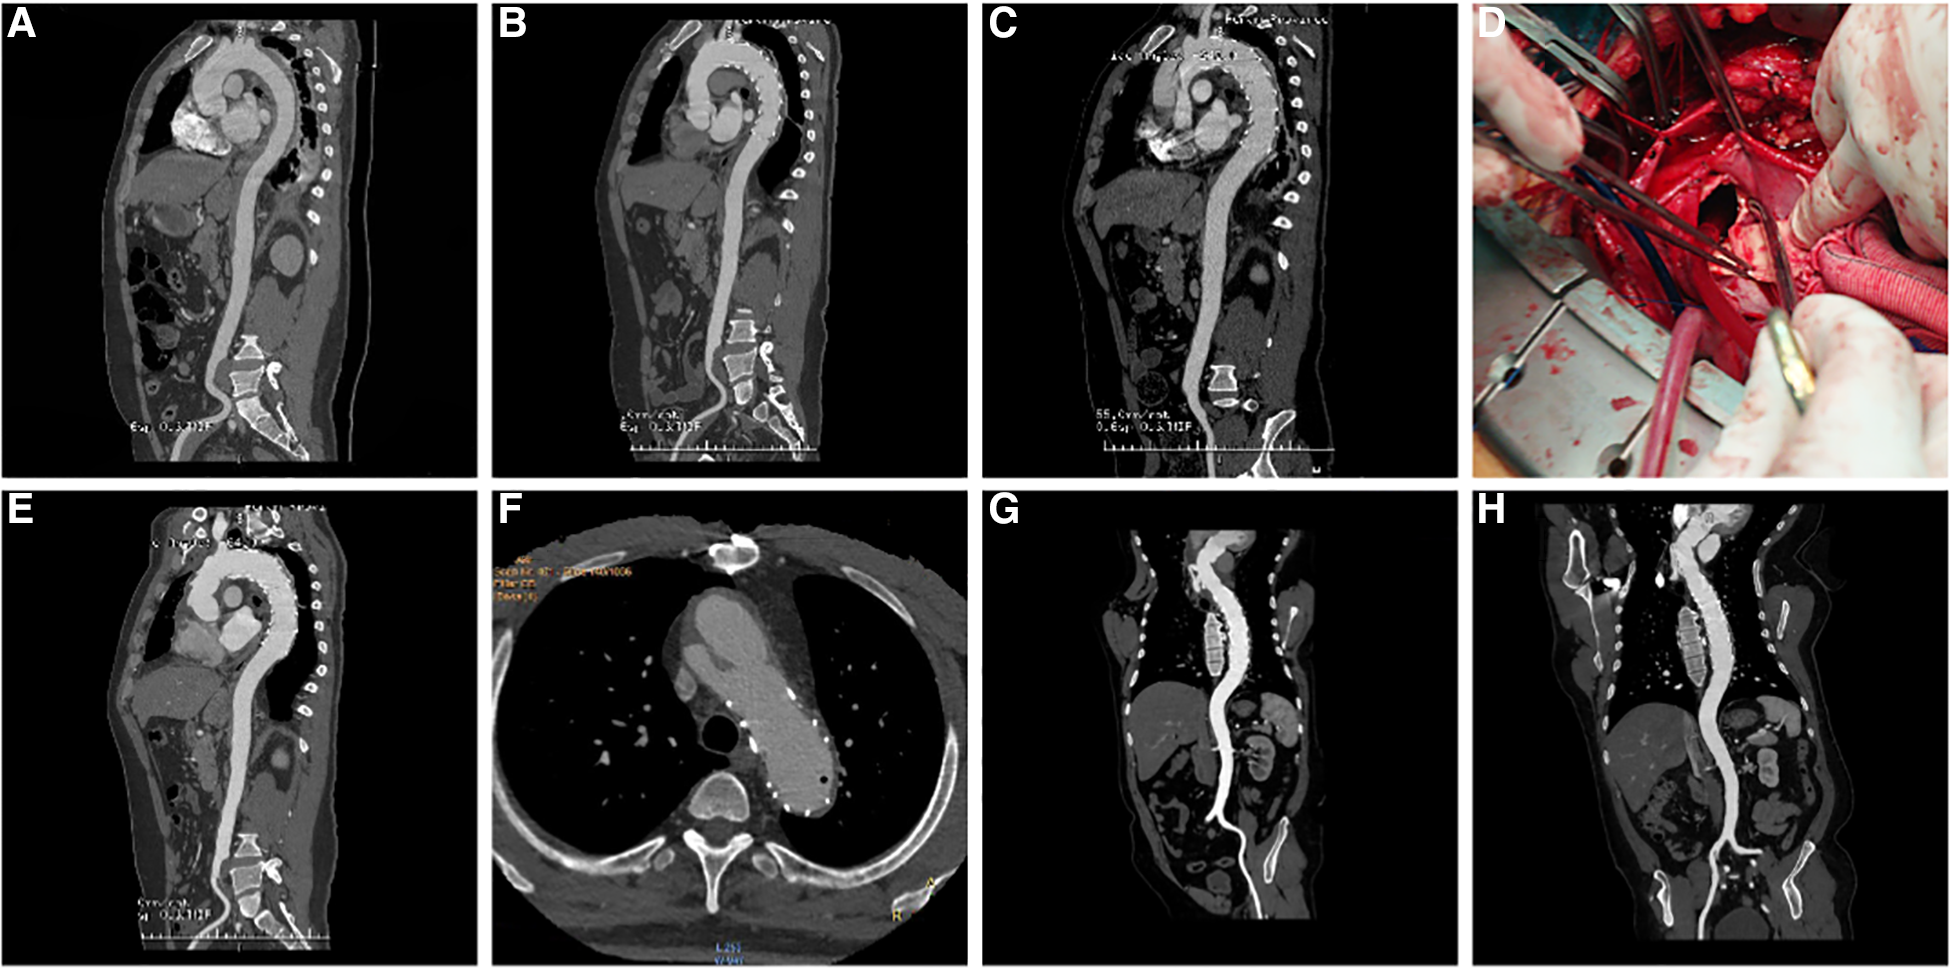

Figure 2

(A) three-dimensional (3D) reconstruction of preoperative surgery CTA showed intramural hematoma of descending aorta; (B) CTA demonstrated that the intramural hematoma was thinner than that before ten days following TEVAR; (C) five weeks following TEVAR, 3D reconstruction of CTA showed RTAD; (D) “ascending aortic replacement, hemi-arch replacement, and stented elephant trunk” was implemented in the emergency, and the entry tear was at the proximal stent; (E) CTA two weeks following the surgery showed changes in the ascending aorta and the arch after replacement; (F) At 90 months after the first surgery, local dissecting aneurysms at the arch were observed; (G) “ascending aortic replacement, total arch replacement, and stented elephant trunk” were performed during the second surgery; (H) CT re-examination on the nine months after second surgery. CTA, CT angiography; TEVAR, Thoracic Endovascular Aortic Repair; RTAD, Retrograde Type A Aortic Dissection; 3D, three dimension.

Among the 18 patients (13 males, five females; mean age, 56.78 years [range, 38–79 years]; Table 2). RTAD occurrences were observed at different time points. Specifically, ten patients with RTAD happened within the TEVAR perioperative period, with two cases during the surgery, six cases occurred within three months, two cases occurred after one year, and the longest interval being 72 months following TEVAR. The longest follow-up period was 130 months, and the shortest was only one day in RTAD group. Four patients were lost to the follow-up. Seven patients died during the follow-up period. TEVAR was initially implemented in 17 cases, while the operation procedure was temporarily altered in one case. The SG utilized comprised ten cases of Medtronic Vialiant, three cases of Cook Zenith, three cases of Gore TAG, and one case of Shanghai MicroPort Castor integrated branching stent. The position of the new entry in 13 RTAD patients was at the proximal region of the SG, and five instances were more than 2 cm distant from the proximal region of the SG. Besides, 17 cases were at the greater curvature of the aorta, and 1 case was at the lesser curvature. It is noteworthy that two cases developed RTAD during the operation. Although the initial surgical plan for case six was to perform a thoracotomy with ascending aorta IA/LCCA bypass and TEVAR, an interim and urgent change was made to perform ascending aortic replacement, total arch replacement with frozen elephant trunk. This decision was prompted by the presence of a dissection observed during the clamping of the ascending aortic wall while reconstructing the branches of the arch. This patient was discharged from the hospital following a satisfactory recovery and was lost to follow-up. In another case with intramural hematoma of TBAD, dilation of a narrow TAG stent with a GORE trilobate balloon resulted in a new entry at the greater curvature of the proximal region of the SG. As a remedial measure, the patient underwent rescue implantation of the second TAG stent after an emergency LCCA-LSA bypass. The patient showed good recovery and remained in a stable condition during the last follow-up. Six of the remaining 16 RTAD patients underwent successful surgical repairs. Case 2 with a favorable outcome and a follow-up of 130 months, was the only one that respectively had ascending aortic replacement, hemi-arch replacement with frozen elephant trunk and ascending aortic replacement, total arch replacement with frozen elephant trunk due to the pain in the chest and back at postoperative five weeks and 90 months (Figure 2). In 10 RTAD patients treated conservatively, seven deaths occurred, and three patients were lost to follow-up. Case one with ascending aorta hematoma formation but no clear entry tear developed RTAD in the perioperative period. At six months of follow-up, the ascending aortic entry tear was visible and located at the proximal portion of the SG. At 33 months of follow-up, stent induced new entry (SINE) occurred at the distal part of SG. At 46 months of follow-up, both proximal RTAD and distal SINE advanced. He died at 56 months due to acute left heart failure combined with mitral valve prolapse (Figure 3). The characteristics of 18 patients complicated with RTAD during or after TEVAR were presented in Table 2.